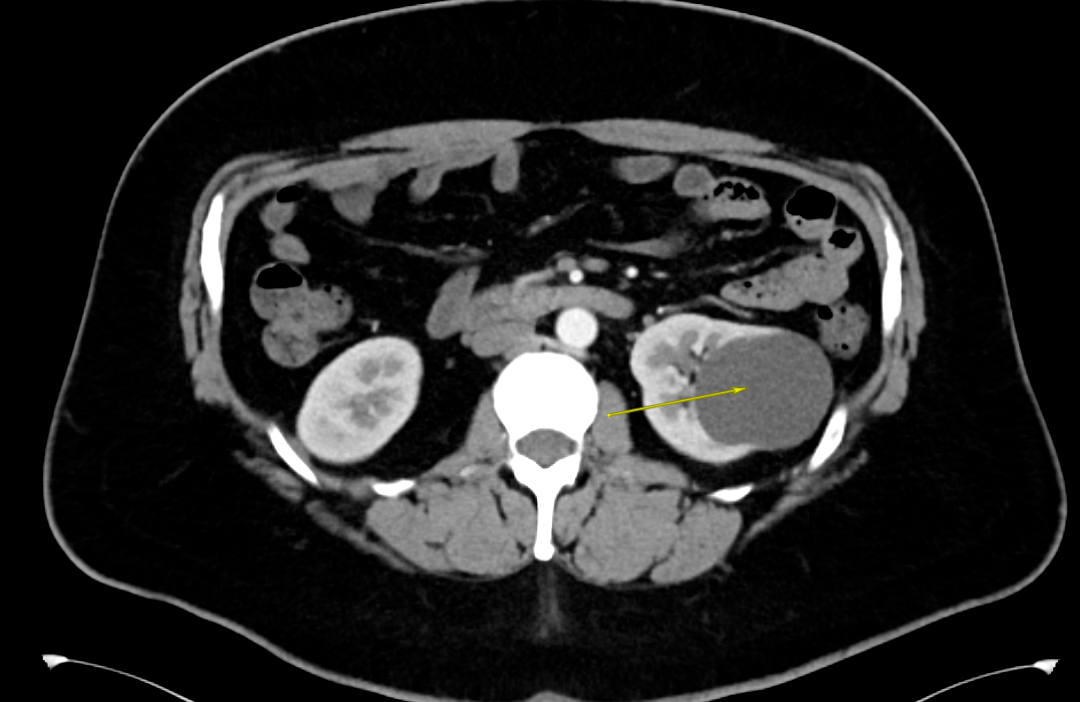

1个月前,Adam感觉到左侧腰背部偶尔会有阵发性胀痛不适的情况,于是做了泌尿系彩超,发现左肾的囊肿已经超过6cm了 。

经过一系列的检查,詹绍洋主任诊断Adam是单纯性肾囊肿,安排住院 。

詹绍洋主任决定在全麻下行腹腔镜下左肾囊肿去顶术,将肾囊肿囊壁进行切除,切除这部分囊壁后原先肾囊肿的完整性就被破坏,它的张力也就随之消失,切除囊壁的肾脏部位就基本不会再次积聚囊液产生压力从而再次形成囊肿 。